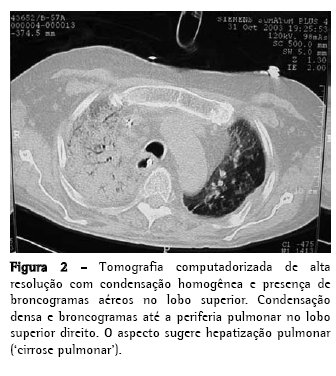

Homem, 56 anos, com diagnóstico de FPI (clínicofuncional-tomográfico-patológico) há cinco anos, evoluiu progressivamente com dispnéia a mínimos esforços e tosse mucóide escassa, intensa e de difícil controle. Apresentava, no mês do transplante pulmonar, hipoxemia e hipercapnia (PaO2 57 mmHg e pressão parcial de dióxido de carbono no sangue arterial 45 mmHg, em repouso e no ar ambiente ao nível do mar), DCO 29% do previsto, capacidade vital forçada 40,8% (1,41 L) e o volume expiratório forçado no primeiro segundo 52,6% (1,31 L). A cintilografia perfusional pulmonar demonstrava fluxo arterial de 76,7% para o pulmão direito e 23,3%, para o pulmão esquerdo. Os exames laboratoriais para o diagnóstico de doenças do colágeno e o inquérito epidemiológico para as doenças intersticiais conhecidas foram negativos. Durante os cinco anos de acompanhamento, tinha utilizado corticosteróides (prednisona 0,25 a 1 mg/kg/dia), imunossupressores (azatioprina ou ciclofosfamida 0,5 a 2 mg/kg/dia) e antifibrótico/imunomodulador (interferon-.1b) por quatro meses. O transplante foi unilateral à esquerda, correspondendo à menor perfusão arterial e maior intensidade do acometimento do interstício pela tomografia computadorizada de alta resolução (TCAR). No pós-operatório imediato evoluiu com instabilidade torácica devido à fratura de três arcos costais, em decorrência da tração de costelas osteopênicas durante o fechamento da ferida cirúrgica, e com isquemia de reperfusão pulmonar grave (relação PaO2/fração inspirada de oxigênio = 124). Permaneceu em ventilação mecânica (VM) invasiva por dez dias, traqueostomizado, e recuperando-se progressivamente da hipoxemia. O esquema de imunossupressão iniciado foi composto pela ciclosporina 5 mg/kg de 12/12 h, prednisona 0,5 mg/ kg/dia e azatioprina 2 mg/kg/dia, além do anticorpo anti-receptor da interleucina-2 basiliximab no 1º e 4º dias pós-operatório e da metilprednisolona 1 g no pré-operatório. Obteve alta da unidade de terapia intensiva para o quarto da unidade semi-intensiva, mas no 8º dia na unidade semiintensiva houve exacerbação da dispnéia, associada ao retorno da tosse seca e de progressiva estertoração crepitante em todo o hemitórax direito, sendo re-encaminhado para a unidade de terapia intensiva. Uma nova avaliação foi feita através de TCAR, broncofibroscopia com lavado broncoalveolar (LBA) e biópsia transbrônquica do lobo inferior esquerdo e do lobo superior direito. Todas as culturas foram negativas, o LBA tinha padrão neutrofílico, sem eosinófilos ou macrófagos com hemossiderina, e o histopatológico não foi conclusivo. Foi realizada arteriografia pulmonar e, posteriormente, vídeotoracoscopia com biópsia pulmonar em três diferentes regiões do lobo superior direito para assegurar a representatividade da doença (Figuras 1 e 2). A arteriografia não demonstrava doença tromboembólica.

De acordo com os dados da International Society for Heart and Lung Transplantation de 2006,(2) mais de 50% dos transplantes para FPI são unilaterais. A FPI é um modelo ideal de doença para o transplante unilateral, pois a ventilação e a perfusão são direcionadas preferencialmente para o enxerto.(17) No entanto, o pulmão nativo pode ser fonte potencial de complicações, inclusive como 'hepatização' do pulmão nativo, fato ainda não relatado na literatura.

As imagens radiográficas demonstravam condensação dos lobos médio, superior e inferior direito, e o diagnóstico estabelecido foi de exacerbação da FPI no pulmão nativo, caracterizado principalmente pelo aspecto histológico de PIU (infiltrado não-uniforme e multifocal, com espessamento inflamatório e fibroso do interstício alveolar, cistos pulmonares, fibrose peribronquiolar, hiperplasia alveolar e ausência de membranas hialinas) e pelas ausências de crescimento microbiano nos tecidos pulmonares e de descompensação cardiovascular. Sabe-se que na FPI, o pulmão se torna progressivamente colapsado, o que pode simular imagens de condensações pulmonares. A variante acelerada da FPI está sendo recentemente descrita e deve ter o seu diagnóstico caracterizado pela exclusão de outras causas de exacerbações. A literatura menciona, no transplante pulmonar unilateral, a progressão crônica da FPI no pulmão nativo, não havendo relatos de progressão aguda. Este é o primeiro caso da literatura nacional descrito como FPI na sua fase acelerada.